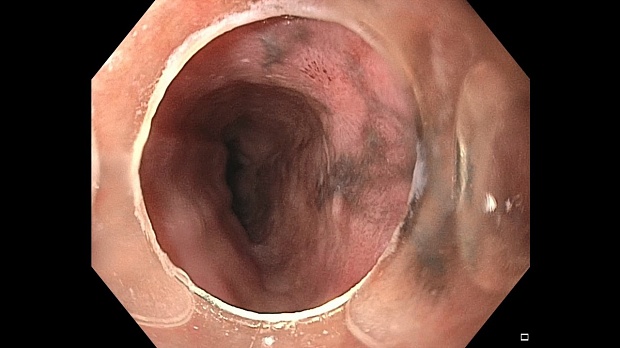

Иллюстрация №1: Эндофото. Сидероз нижней трети пищевода, осмотр в белом свете

Согласно полученным данным - в среднегрудном и нижнегрудном отделах пищевода определялась проксимальная граница плоских неправильной формы поверхностных рубцов суммарной протяженностью до 8,0 см. На этом фоне в зонах поверхностных рубцов по задней полуокружности визуализировались участки гиперпигментации в темный цвет (Рис. 1). При исследовании в режиме Dual Focus было отмечено наличие мелких (до 0,001 см) черно-коричневых включений, расположенных субэпителиально - в строме слизистой оболочки, сливания их в единый конгломерат не определялось (Рис. 2). При эндосонографии с применением минидатчика с частотой сканирования 20МГц выявлено, что все слои стенки четко дифференцируются, не утолщены, в слизистой оболочки визуализированы мелких гиперэхогенные включения с эхотенями (Рис. 3).

В пищеводе в шейном его отделе на уровне 16 см от резцов циркулярно визуализированы единичные синюшные флебоэктазии размерами до 0.5 см. Дистальнее пищевод визуально не изменен до уровня 28 см от резцов, где определяется проксимальная граница плоских неправильной формы поверхностных рубцов, распространяющихся до уровня 36 см от резцов. На этом фоне в зонах поверхностных рубцов по задней полуокружности визуализированы участки гиперпигментации в черно-коричнеый цвет. При осмотре в режиме Near Focus с увеличением - между зон пигментации определяются расширенные капилляры типа II по Inoue-классификации. При биопсии отмечена десквамация плоского эпителия, визуализированы мелкие черно-коричневые включения в строме слизистой оболочки, размеры их до 0,001 см, сливания их в единый конгломерат не отмечается. При эндосонографии с датчиком 20Мгц в исследуемой зоне в слизистой оболочке определяются гиперэхогенные включения, в то время как в подслизистом слое - зоны со сниженной эхогенностью. При биопсии отмечается уплотнение ткани, однако истинной фрагментации не определяется. Уровень Z-линии совпадает с уровнем анатомического кардиоэзофагеального перехода. Розетка кардии эластичная, смыкается не полностью, расположена на уровне пищеводного отверстия диафрагмы.